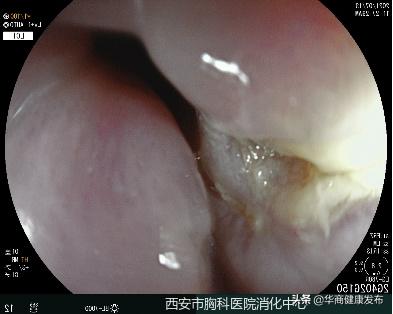

7月13日下午,西安市胸科医院消化内科门诊来了一位82岁的老人,因为进食过程不小心,一根鱼刺卡在了食管内已经超过24小时,就诊多家医院,无法取出异物。张蓉医生仔细询问了患者病情,迅速为老人完善了内镜和异物取出术的相关检查,以尽快解除险情,避免异物进一步扎穿食管,增加治疗的创伤和复杂性。

情况紧急,张蓉医生立即为老人行胃镜下异物取出术,仅用10分钟,张蓉医生用异物钳将鱼刺成功取出。老人安全返回病房,经观察没有任何不适,恢复正常进食。

鱼刺约1.5cm长,位于颈7水平,食道前壁偏右侧